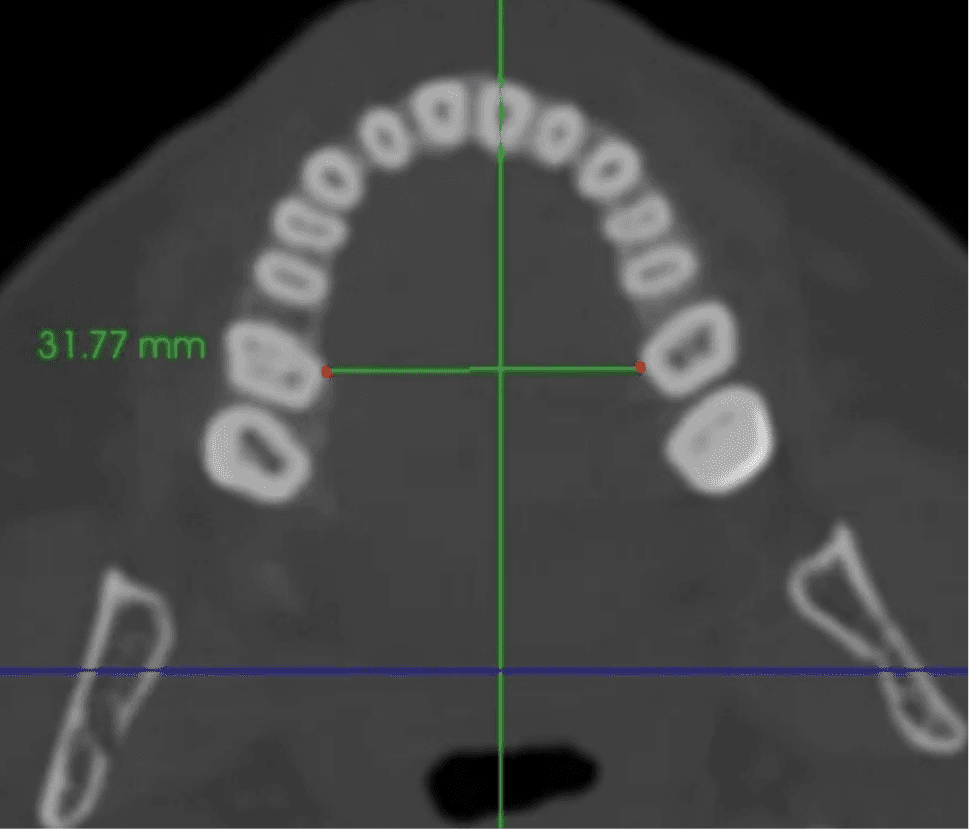

Dr. Tara Griffin is a Vivos provider who underwent treatment herself. She was diagnosed with moderate obstructive sleep apnea in 2011, with an AHI of 24 events per hour. What distinguishes her case is the depth of documentation: her progress was tracked not only by sleep studies but by direct measurement of her dental arch, the structural width of the upper jaw, over the course of eight years. Her arch measured 31.5 millimeters before treatment. By 2013, after approximately 10 to 15 months of treatment, it had expanded to 35.5 millimeters. At her 2019 follow-up, 37.5 millimeters.

Jaw Width - 31.5mm

Before Treatment, 2011